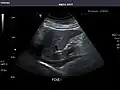

Pancreas -